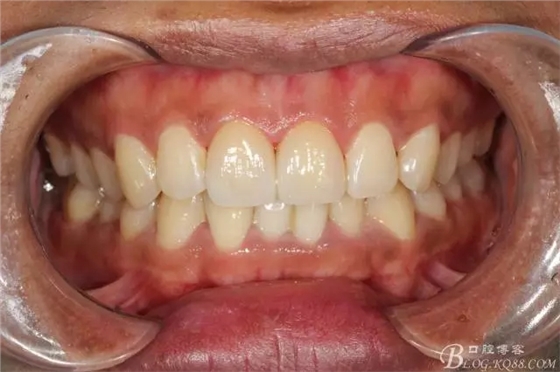

粘接完成即刻照

即刻照局部放大